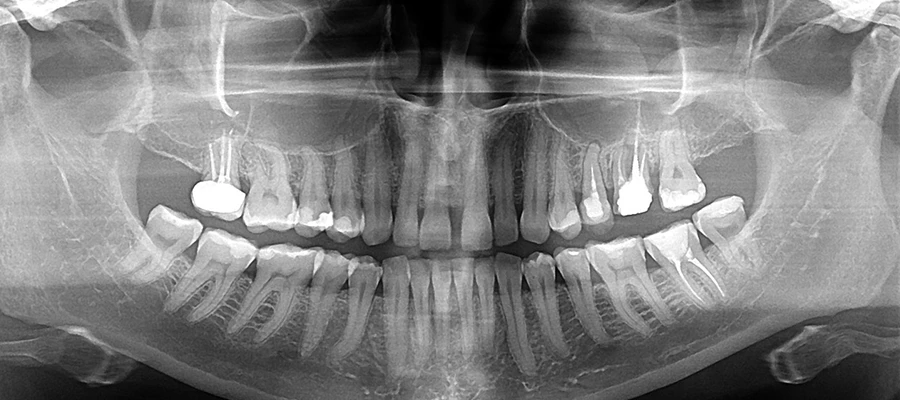

Panoramik röntgen: panoramik x-ray ya da ilk adı ile panorextir. Panoramik röntgendeki x-ışınlarının verdiği radyasyon oranı diğer yöntemlere göre daha azdır. Sonuç hızlı bir şekilde alınır. Bu yöntemde özellikle diş ağrıları olan hastalar için çok büyük zaman avantajı vardır. Panorex yani panoramik röntgen, diş doktorlarının yapacağı, diş implant ameliyatları planlamasında da çok gereklidir. Panoramik röntgen diş hekimine hastanın, burun bölgesini, sinüslerini, alt ve üst çene eklemlerini, dişlerini ve onu çevreleyen kemik yapısını gösterir. Panoramik röntgen filmi kistleri, tümörleri, kemik düzensizliklerini ve çok daha fazlasını ortaya çıkarmaktadır.